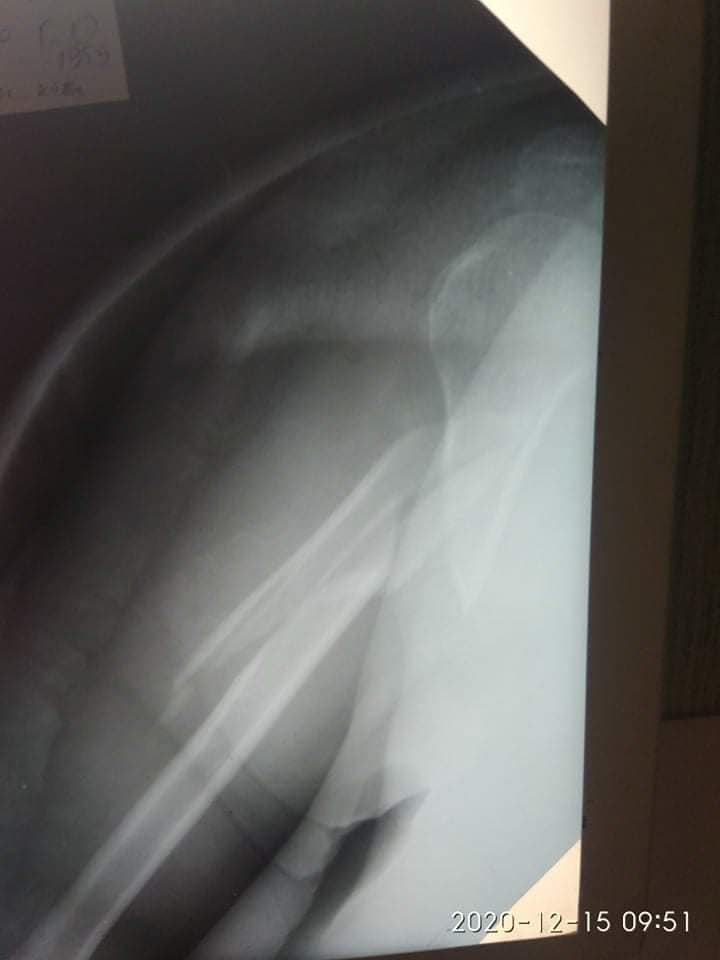

Діагноз: Закритий багатовідламковий перелом діафізу правої плечової кістки", - йдеться в дописі.

21 грудня їй провели 4-ьох годинну операцію - остеометалосинтез правої плечової кістки за допомогою LCP проксимальної Philos пластини та гвинтів.